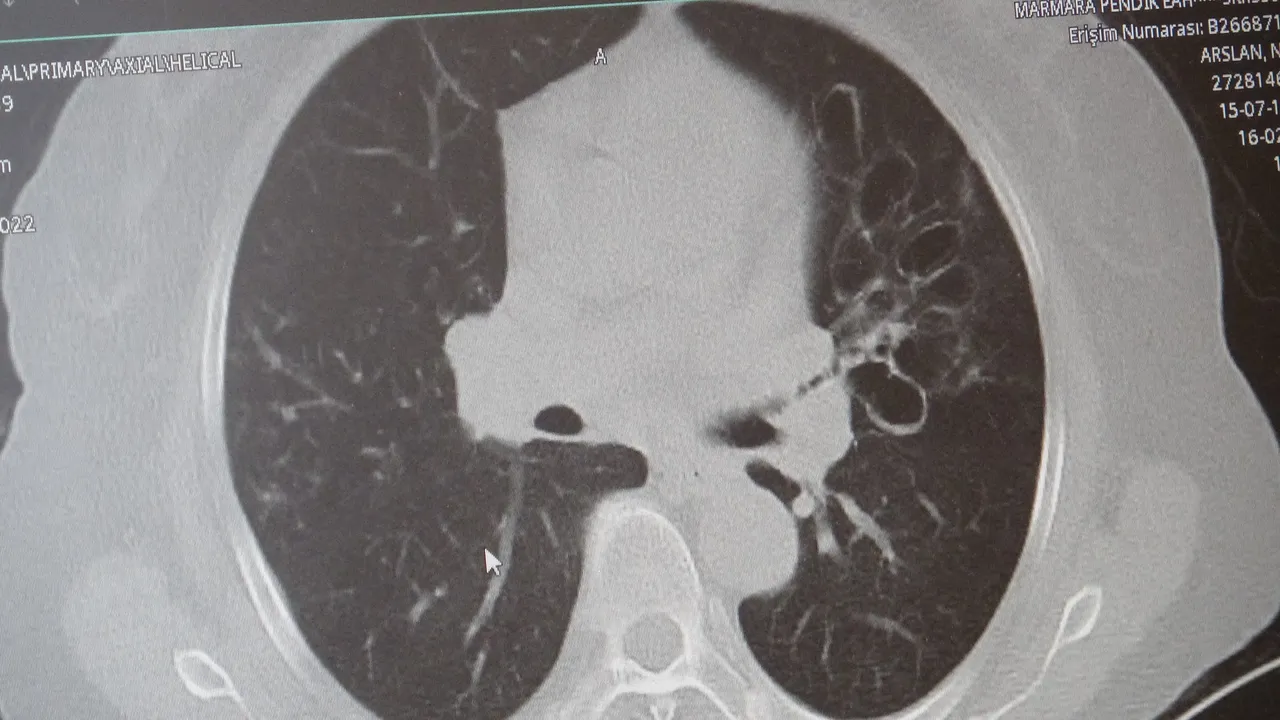

KOAH toplumda sık görülen bir hastalıktır ve yaklaşık toplumda bunu yüzde 10 civarında görüyoruz. KOAH, zararlı maddelerin akciğeri parçalamasıyla oluşan bir rahatsızlık ve bunun da en önemli nedeni sigara. Vakaların aşağı yukarı yüzde 85’i sigara kullanımından kaynaklıdır. Bunun dışında hava kirliliği, iş yerlerinde kimyasal maddelere maruz kalma ve enfeksiyonlar da yine KOAH'ın nedenleri arasındadır. KOAH'ın önemi şu; bugün Dünya Sağlık Örgütü'nün (DSÖ) dünyada insanları öldüren hastalıklar listesinde ilk 10'da 4'üncü sırada yer alıyor.

Karakurt, KOAH’ın akciğer dokusunu tahrip eden bir hastalık olduğunu ve bu nedenle de hastaların enfeksiyona açık hale geldiğine dikkat çekti:

Akciğer dokusunun tahrip olduğu her durumda hastaların enfeksiyona karşı eğilimi artar ve enfeksiyona yakalandıkları zaman bunun geçmesi güç olur. KOAH'lı hastalar zatürre geçirdikleri zaman öksürük ve balgam artışı gibi birtakım belirtiler gelişir. Ayrıca ateşin 38,5 derecenin üstüne çıkması, nefes darlığının artması, titremeyle birlikte ateşin yükselmesi ve bir takım bilinç bozukluğu gibi belirtiler hastanın zatürre olduğunu gösterebilir. Bu nedenle hastaların erkenden doktora başvurmaları önemlidir.